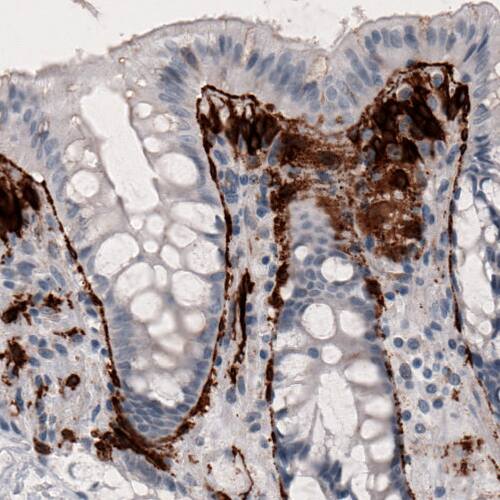

Staining of human colon shows strong immunoreactivity in pericryptal sheath cells.